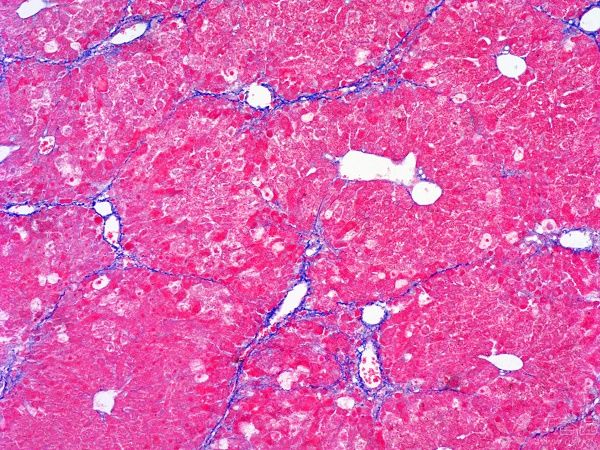

MASSON染色實(shí)驗(yàn)的目的是為了在組織學(xué)研究中可視化并區(qū)分不同類(lèi)型的纖維,特別是膠原纖維和肌纖維。MASSON染色實(shí)驗(yàn)?zāi)康挠?a style='text-decoration: underline;color: rgb(84, 141, 212);' style="text-decoration: underline;color: rgb(84, 141, 212);" href="http://www.tjdqdt.com/shiyan/view/heranse.html" target="_self">普拉特澤生物病理染色平臺(tái)總結(jié)分享,病理組織染色平臺(tái)為廣大科研實(shí)驗(yàn)人員提供MASSON染色實(shí)驗(yàn)服務(wù),先一起來(lái)學(xué)習(xí)學(xué)習(xí)關(guān)于MASSON染色實(shí)驗(yàn)?zāi)康?/strong>

這種染色方法通過(guò)特定的化學(xué)反應(yīng)和染料選擇,使得不同類(lèi)型的纖維在顯微鏡下呈現(xiàn)出不同的顏色,從而便于研究者對(duì)組織結(jié)構(gòu)和病變進(jìn)行準(zhǔn)確的觀察和分析。

㈠:MASSON染色通過(guò)特定的染色劑:能夠使膠原纖維和肌纖維分別呈現(xiàn)出不同的顏色,從而實(shí)現(xiàn)對(duì)這兩種重要組織成分的精準(zhǔn)區(qū)分。這對(duì)于后續(xù)的組織學(xué)研究具有非常重要的意義。

㈡展示組織纖維化程度:作為一種重要的組織纖維化觀察方法,MASSON染色能夠清晰地顯示出組織中的纖維結(jié)構(gòu),包括膠原纖維的排列、形態(tài)和數(shù)量等。通過(guò)對(duì)這些信息的觀察和分析,研究人員可以準(zhǔn)確地評(píng)估組織的纖維化程度,為進(jìn)一步的研究和治療提供重要依據(jù)。

MASSON染色實(shí)驗(yàn)的目的是為了在組織學(xué)研究中可視化并區(qū)分不同類(lèi)型的纖維,特別是膠原纖維和肌纖維。通過(guò)這種方法,研究者可以深入了解組織的結(jié)構(gòu)和功能,為疾病的預(yù)防、診斷和治療提供重要的參考信息。